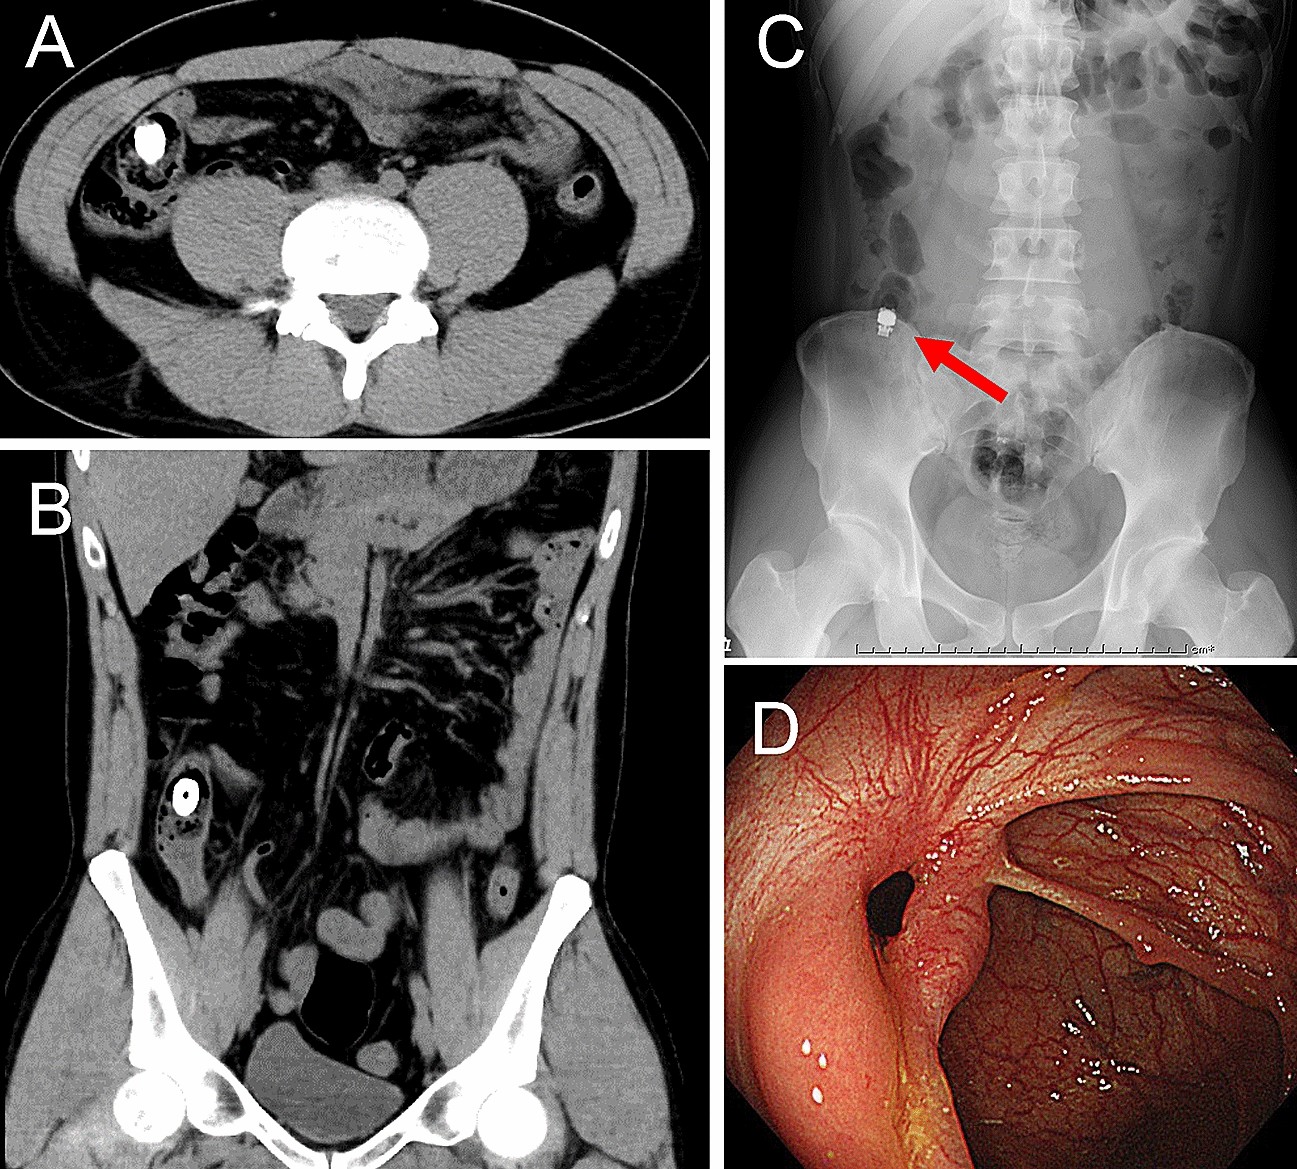

Figure 3

SBCE retention case caused by CT misjudgement of PC in a patient with Crohn’s disease. Plain computed tomography (CT) images show that the PC seemed to be in the ascending colon; axial CT image (A), coronal CT image (B). X-ray scan confirms SBCE retention (arrow) in the terminal ileum after 2 weeks (C). Colonoscopic image confirms ileocecal valve stenosis, which was treated with balloon dilatation (D).